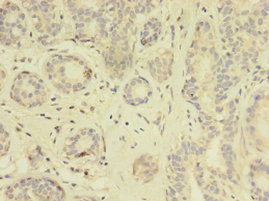

Immunohistochemistry of paraffin-embedded human colon cancer using CSB-PA023577HA01HU at dilution of 1:100

Immunohistochemistry of paraffin-embedded human breast cancer using CSB-PA023577HA01HU at dilution of 1:100